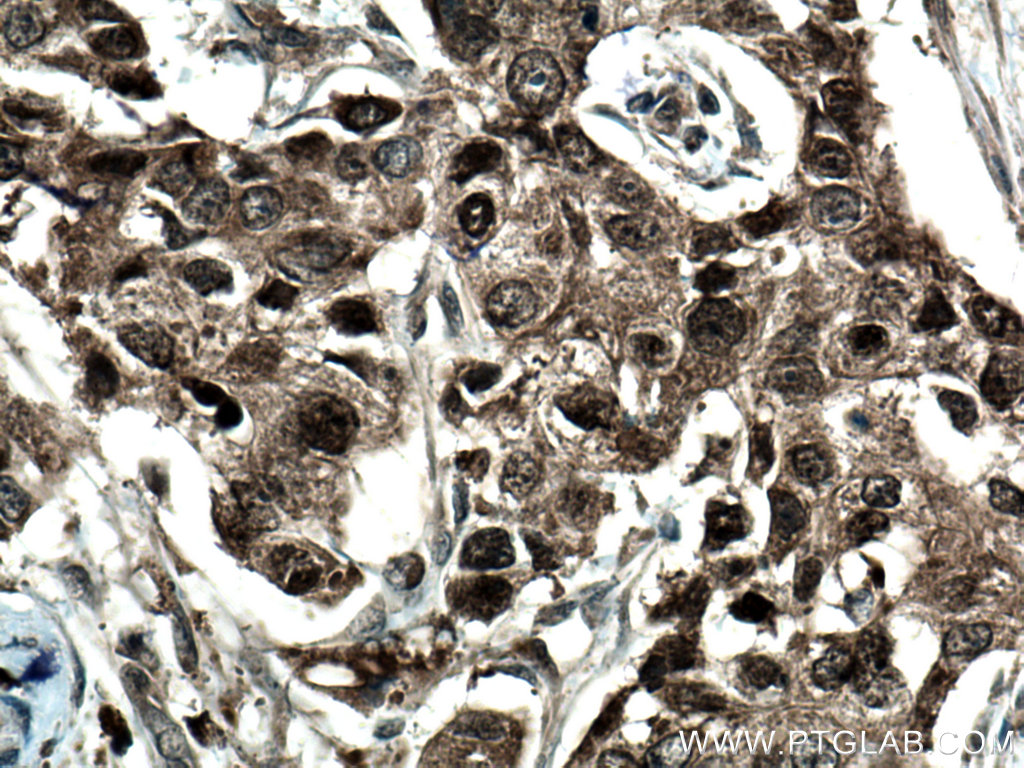

| Positive IHC detected in | mouse brain tissue, human breast cancer tissue, mouse testis tissue Note: suggested antigen retrieval with TE buffer pH 9.0; (*) Alternatively, antigen retrieval may be performed with citrate buffer pH 6.0 |

| Immunohistochemistry (IHC) | IHC : 1:50-1:500 |